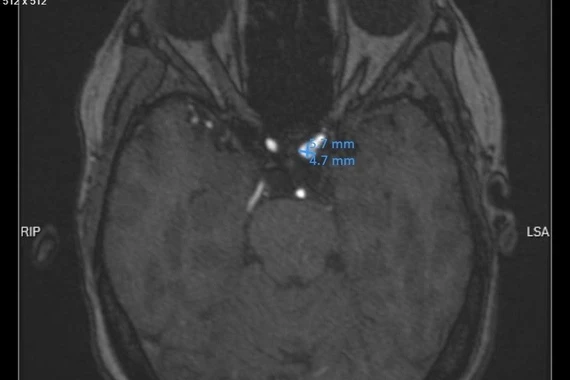

Ảnh minh hoa

BSCKI Nguyễn Văn Tuấn, Bộ môn thần kinh, BV 103: Để chẩn đoán u não và giai đoạn của u não thì phải được khám xét kỹ lưỡng cẩn thận.

Các triệu chứng thường gặp của u não là: Đau đầu, đặc biệt vào buổi sáng và đỡ đần trong ngày; Co giật; Buồn nôn hoặc nôn; Yếu hoặc mất cảm giác ở tay hoặc chân; Mất thăng bằng khi đi lại; Cử động nhãn cầu bắt thường hoặc thay đổi thị giác; Buồn ngủ; Thay đối tính cách hoặc trí nhớ; Thay đổi ngôn ngữ…

Những triệu chứng này có thể do u não gây ra nhưng cũng có thể do các bệnh khác gây ra. Vì vậy, nếu có nghi ngờ tốt nhất bạn nên đưa cháu đi khám.